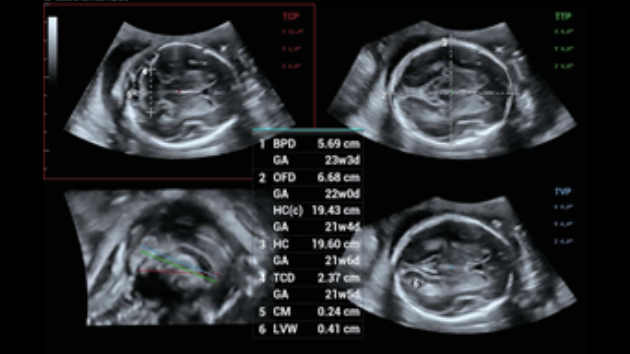

Indipendentemente dalle attività svolte in ospedale o in clinica, oppure se si desidera affinare le proprie capacità nella diagnostica per immagini generale negli ambiti della salute della donna o cardiovascolare, questa serie di soluzioni fornirà potenti strumenti per essere sempre un passo avanti.

Soluzioni di diagnostica per immagini complete con tecnologia ZST+

La piattaforma ZST+ è un'innovazione straordinaria, che rappresenta un'evoluzione nel campo dell'ecografia. Grazie alla trasformazione delle metriche a ultrasuoni dal beamforming convenzionale all'elaborazione basata sui dati di canale, supera la tradizionale limitazione del trade-off tra risoluzione spaziale, risoluzione temporale e uniformità dei tessuti, offrendo una qualità d'immagine eccezionale per infinite soluzioni di imaging con miglioramenti continui.